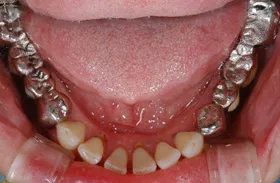

生まれつき歯が生えてこなかったケース

■治療前:生まれつき下顎左右前歯がなく隙間がある

■治療後:矯正治療後、下顎左右3番の2本にインプラント治療

| 主訴 | 生まれつき歯がなく隙間があり、審美障害・咀嚼機能障害がある |

| 治療方法 | インプラント治療 + 矯正治療 |

| 治療期間 | インプラント治療 約6ヶ月 |

| 通院回数等 | インプラント治療 約6回 |

| 費用 | 約94万円(税込) |

| リスク・副作用 | 術後の腫れ・痛み |